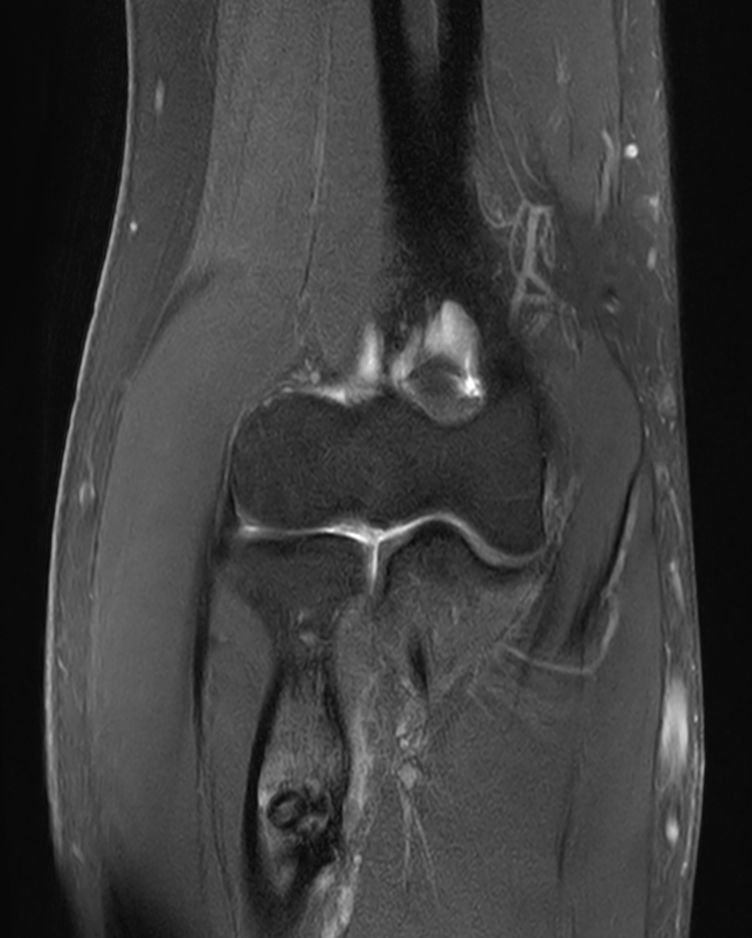

PDw TSE FatSat Compressed SENSE

T1w TSE Compressed SENSE

T2w TSE MultiVane XD FatSat